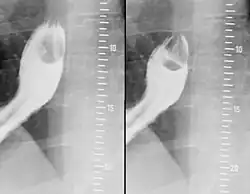

- ↑ T. Schlick, T. Junginger: Abrikossoff-Granulosazelltumor: Ein seltener Tumor des Oesophagus. In: Chirurg. 1997 Sep;68(9), S. 932–935. PMID 9410685